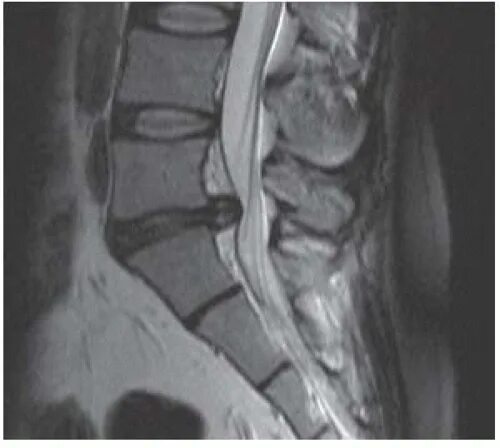

Диффузная грыжа l4 l5